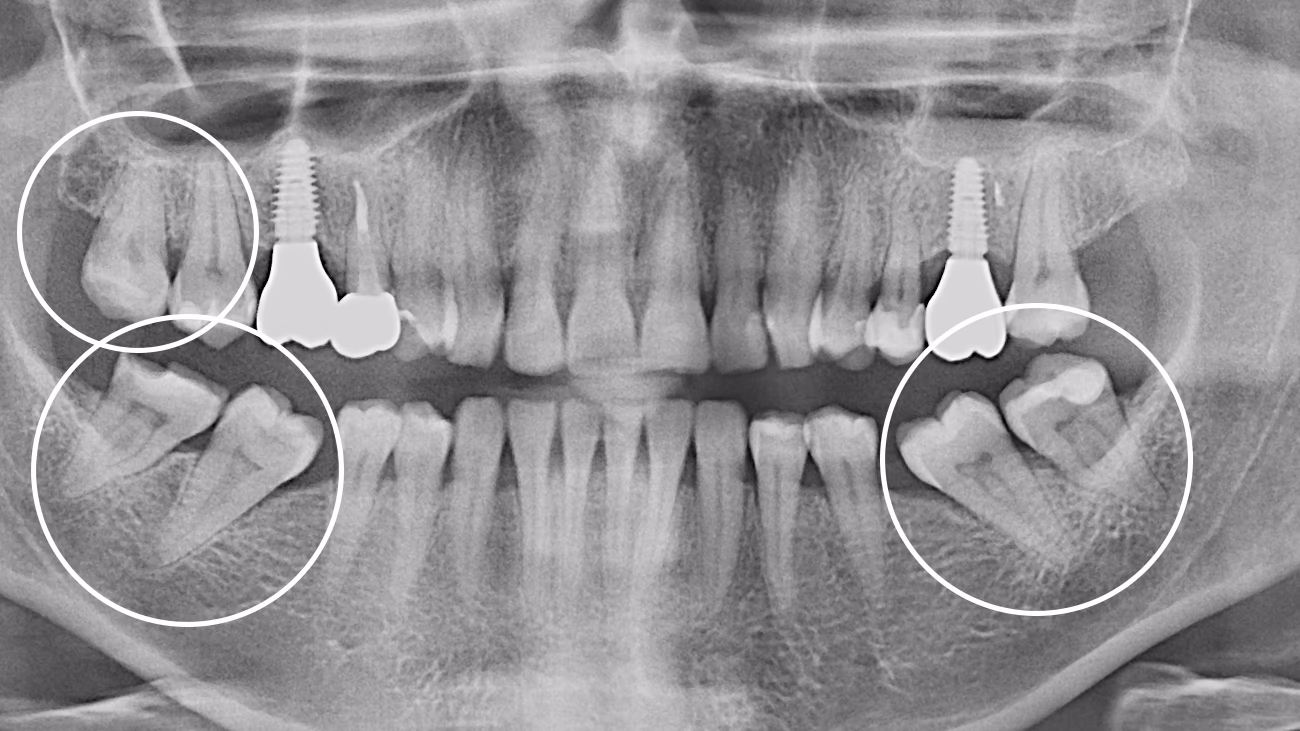

Так. КТ є обов’язковою для точного та безпечного видалення зуба мудрості.

3D-діагностика дозволяє визначити:

• положення зуба

• напрямок росту

• особливості коренів

• близькість до нижньощелепного нерва або верхньощелепної пазухи

У Sergatiy Dental Clinic КТ є обов’язковою перед видаленням зуба мудрості. Без КТ значно підвищуються ризики ускладнень.